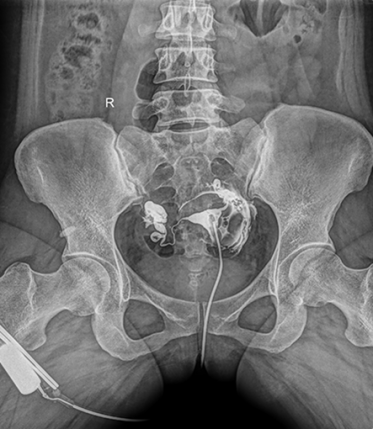

多功能動態(tài)平板DR,采用U型臂結構,具有靜態(tài)DR攝影、數(shù)字透視、數(shù)字造影和可視化攝影的功能。

電動旋轉內平衡結構,可實現(xiàn)快捷擺位,滿足特殊體位的靜態(tài)與動態(tài)檢查。